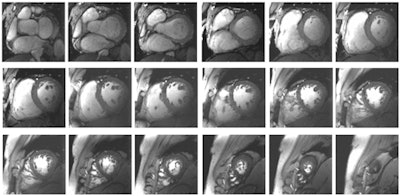

More specifically, 7-tesla MRI should have the unique ability to advance cardiac chamber quantification of the left and the right ventricles using high-density arrays of radiofrequency antennae. Several studies have reported an SNR increase with 7-tesla MRI of 2.1 times compared with 1.5-tesla. The enhanced uniform signal intensity creates high-quality images and high blood/myocardial contrast over the entire heart.

Ultrahigh-field cardiac MRI provides "an unprecedented potential for real-time imaging and addressing some of the shortcomings and physiological constraints of traditional assessments of left ventricular and right ventricular structure and function," noted the authors, citing "accelerated imaging capabilities of free-breathing real-time imaging" of the heart at 7 tesla.